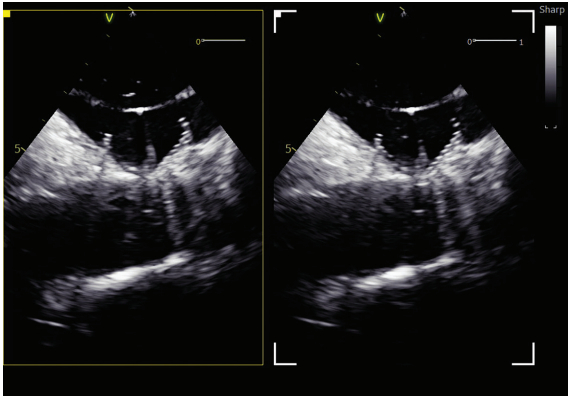

Intraprocedural imaging and mapping were performed using 4D ICE via a 11 French venous sheath and 3D electroanatomic mapping to guide transseptal access, verify lesion delivery, and confirm optimal LAA device position, all under conscious sedation. The 4D ICE provided volumetric, high-resolution visualization of the LA and LAA in real time, while 3D mapping allowed detailed electroanatomic reconstruction and accurate lesion targeting with reduced reliance on fluoroscopy.

A transseptal catheterization was performed using the Faradrive Steerable Sheath (Boston Scientific) and Faraconnect dilator, along with VersaCross Access Solution (Boston Scientific), in the low to mid septum and slightly anterior position to facilitate the ablation and subsequent exchange for the Watchman TruSteer (Boston Scientific) delivery sheath for an optimal ablate-and-close procedure. LAA measurements obtained before ablation were 18 to 19 mm in 3 views (short-axis/mid LA, long-axis, and supramitral). No significant edematous change was observed in the limbus after ablation. A 27-mm Watchman FLX Pro LAAO device was selected, which completely sealed the LAA without residual leak on color flow imaging. Postdeployment measurements were 19 to 20 mm in 3 ICE views, including multiplanar reconstruction using the 4D ICE Nuvision Ultrasound Catheter (Johnson & Johnson MedTech). The patient tolerated the procedure without complications.